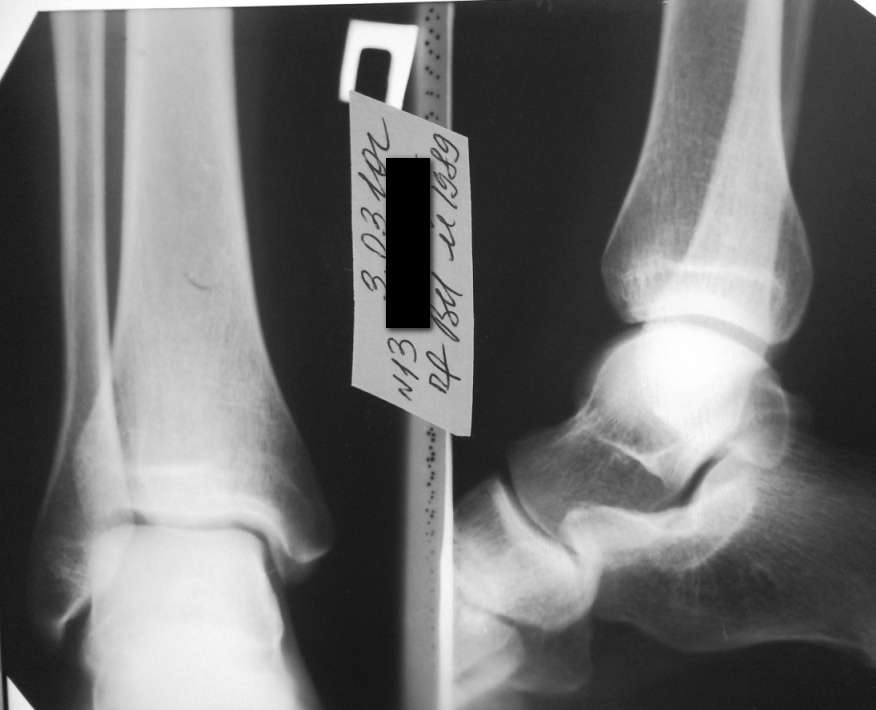

Здравствуйте уважаемые коллеги! Больной 1989 г.р. Беспокоит боль в

области нижней трети правой голени с медиальной стороны, при ходьбе и

пальпации надкостницы большеберцовой кости, по переднемедиальной

поверхности от лодыжки до граници нижней и средней трети.

Болен в течении недели, начало постепенное, без видимых причин.

Травму отрицает. Визуально никаких изменений нет ни в объеме

конечности, ни во внешнем виде кожных покровов. Боль только при

нагрузке, в покое и ночью не болит. Заранее благодарю за высказанные

мнения по поводу диагноза. Снимки прилагаю.